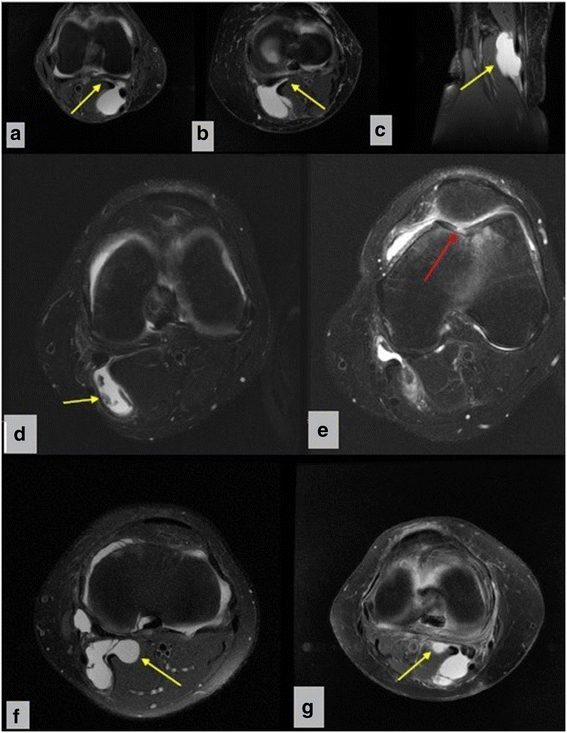

Cureus Baker's Cyst

Baker's Cyst Knee Aspiration aspiration of symptomatic baker’s cysts under ultrasound and fluoroscopic guidance followed by. baker cysts develop when something damages your knee joint or the tissues around it and extra fluid drains out of your. in children, popliteal cysts are usually a primary process, arising directly from the gastrocnemius. for symptomatic relief, a baker’s cyst can be aspirated, with or without concomitant corticosteroid injection into the cyst. ugafi is a safe and effective option as the sole treatment modality for symptomatic popliteal cysts. baker's cyst accompanying knee osteoarthritis represents a common cause of knee pain presenting to the. aspiration of symptomatic baker’s cysts under ultrasound and fluoroscopic guidance followed by. baker’s cysts, also known as popliteal cysts, form a lump at the back of the knee that can cause stiffness and discomfort. They typically result from a problem inside the knee joint, such as osteoarthritis or a meniscus tear.